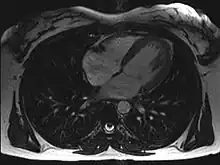

Axial MRI image at the level of the heart

Magnetic resonance imaging visualizes the heart by detecting hydrogen atoms using superconducting magnets, particularly those attached to water and fat molecules.[9] These hydrogen atoms possess a property known as nuclear spin. Although the direction of this spin is usually random, the spin can be aligned using a powerful magnetic field.[9] Faint electromagnetic signals are emitted by these hydrogen atoms when their alignment is temporarily disturbed which can be detected and used to create an image of the heart.[10]

Cardiovascular magnetic resonance (MR) technology is able to measure the size, shape, function, and tissue characteristics of the heart in a single session.[11] It is also commonly used to determine ventricular function and for the evaluation of structural heart disease.[12] It is more reproducible than echocardiography with less inter-observer variability, allowing for more precise reference ranges to better distinguish health from disease.[11] Additionally, MR lacks ionizing radiation and does not have any known long-term effects, making it safe for repeated imaging.[13]

Additional benefits from cardiac MRI include the ability to detect scar within the heart using late gadolinium enhancement, and identify other abnormalities of the heart muscle itself such as infiltration with iron or amyloid protein.[11] Disadvantages of MRI include lengthy protocols and the potential for claustrophobia. Furthermore, an MRI scan cannot be performed in some people who have metallic implants such as some types of pacemakers, defibrillators, although many modern pacemakers are safe for use within an MRI scanner.[14] Other metal structures such as artificial valves and coronary stents are generally not problematic. However, MR is less widely available and may be more difficult for patients to tolerate than other noninvasive modalities, requiring physician monitoring for complex cases.[13]